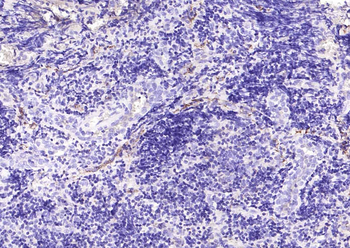

IHC staining of FFPE human tonsil tissue with CD73 antibody (clone NT5E/2545). HIER: boil tissue sections in pH9 10mM Tris with 1mM EDTA for 10-20 min and allow to cool before testing.

IHC staining of FFPE human tonsil tissue with CD73 antibody (clone NT5E/2545). HIER: boil tissue sections in pH9 10mM Tris with 1mM EDTA for 10-20 min and allow to cool before testing.